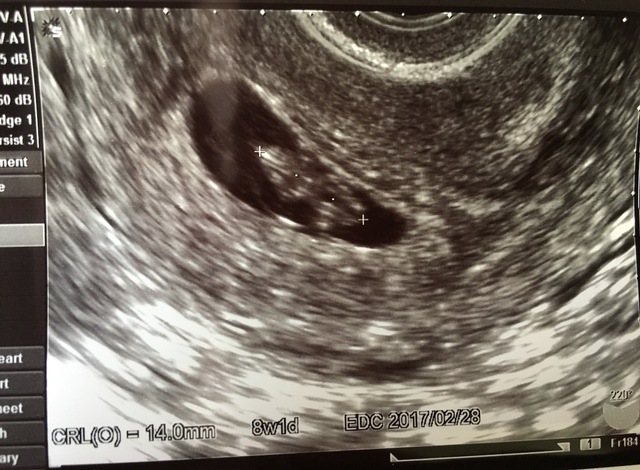

8週1日(8w1d・女の子)| あさみ0601 さん(29歳)

エコー写真撮影時のエピソード:

初めて行ったときは8週なのに心音がきこえず、とても心配でした。翌週の9週ではちゃんときけたので一安心でした。

妊娠がわかったときはとてもうれしくて、思わずにやけるほどでした。主人や両親も喜んでくれましたし、そこから安定期に入り、無事出産できて本当に良かったです。